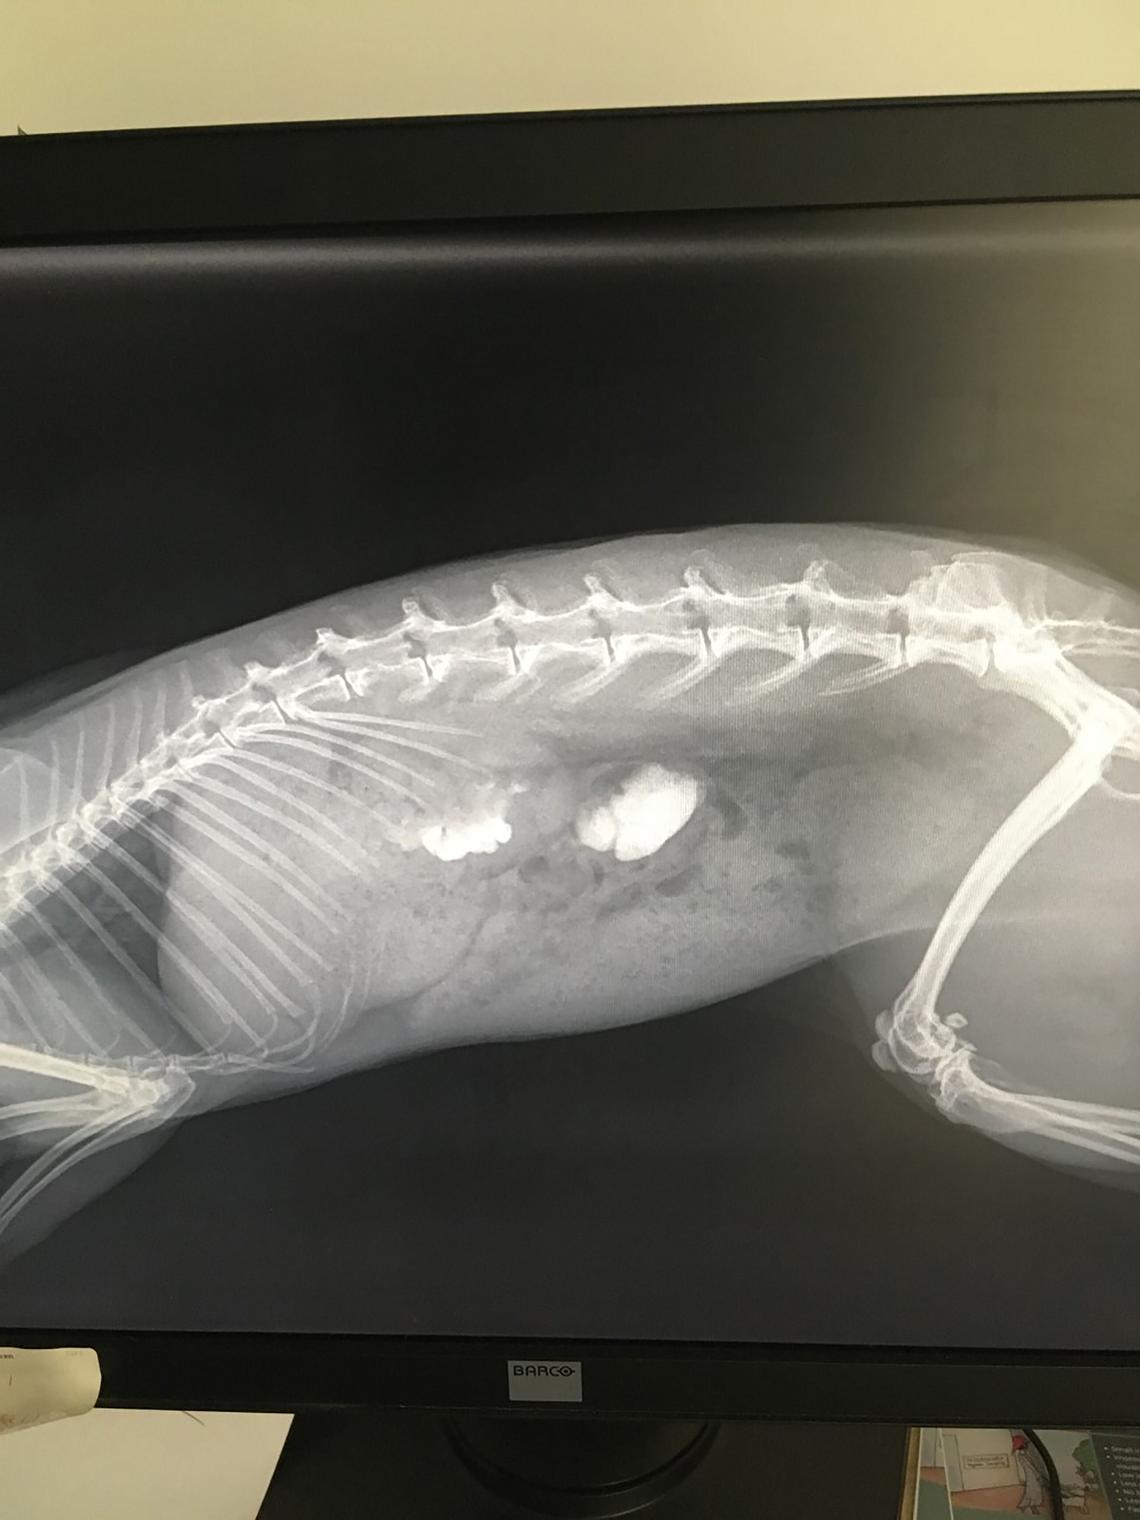

Osteosclerosis. (A) The skeleton of a rabbit with advanced renal How Long Do Rabbits Live With Kidney Failure This article will explore chronic renal disease in rabbits. in this blog post, we will discuss the critical indicators of kidney disease in rabbits, how to recognize symptoms, and what actions you can. here's an overview of the symptoms, diagnosis and treatment approach for kidney failure in rabbits:. the permanent effects of kidney disease will depend on. How Long Do Rabbits Live With Kidney Failure.